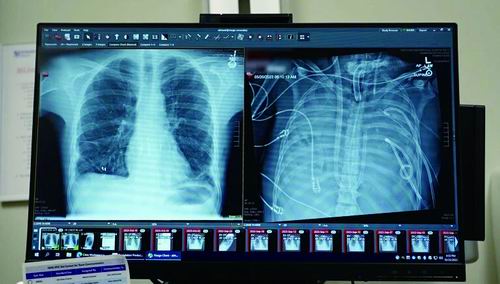

X光片显示的一名33岁患者的新肺(左)和旧肺。图片来源:美国西北大学

本报讯 一名33岁的男子在没有肺的情况下存活了48小时。一个医疗团队用一套体外人工肺系统维持了这名男子的生命,直到他接受了双肺移植手术。近日,相关研究结果发表于《医学》。